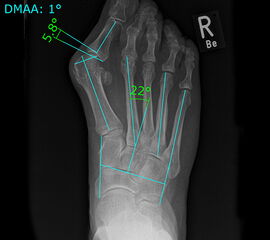

• Folgende Winkel können präoperativ zur Erleichterung der Planung am Röntgenbild eingezeichnet werden:

• IMW (Intermetatarsalwinkel).

• HVW (Hallux valgus-Winkel).

• DMAA (Distal Metatarsal Articular Angle) – Planung der ggf. notwendigen Reverdin-Isham-Osteotomie.

• PPAA (Proximal Phalangeal Articular Angle) – Planung der ggf. notwendigen Akin-Osteotomie.

• VAW (Vorfußadduktionswinkel) – Planung der Ausrichtung der DMMO (Distalen minimalinvasiven Metatarsale Osteotomien).

Einschränkend ist anzumerken, dass o.g. Winkel projektions- und rotationsabhängig sind 15. Daher ist intraoperativ die Planung anhand von Bildverstärkeraufnahmen zu verifizieren und ggf. anzupassen.

Der präoperative AOFAS-Score betrug 41,5 Punkte und konnte postoperativ auf durchschnittlich 86,2 Punkte verbessert werden (p<0,005). Der IMW reduzierte sich von Ø 16,7° (8,5°-20,3°) präoperativ auf Ø 7,14° (6,1°-9,5°) (p<0,005). Ebenso konnte der HVW von präoperativ Ø 45,2° auf postoperativ Ø 9,4° (p<0,005) korrigiert werden. Durch die Durchführung der modifizierten, lateralisierenden DMMO veränderte sich der präoperative VAW von Ø 23° (19,3°-33,5°) auf Ø 15,6° (13°-17,2°; p<0,004).